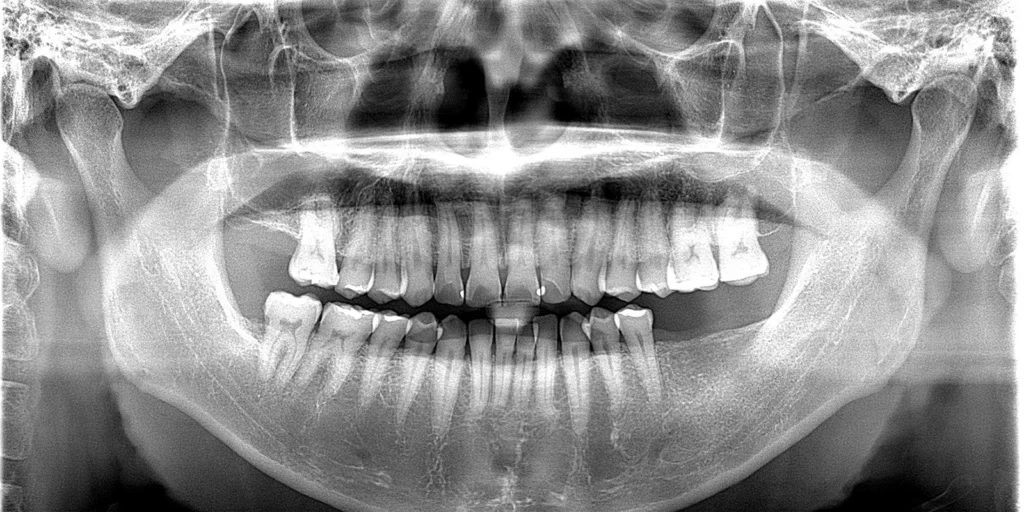

術後のレントゲン写真

今回、ご紹介した手術方法以外にもインプラント手術には、患者様の状態によって様々なオペの方法があります。

また、当院ではインプラントメーカーを複数用意しており、そのそれぞれについて術式は異なります。今回使用したのは、ストローマンというインプラントメーカーのBLXインプラントです。